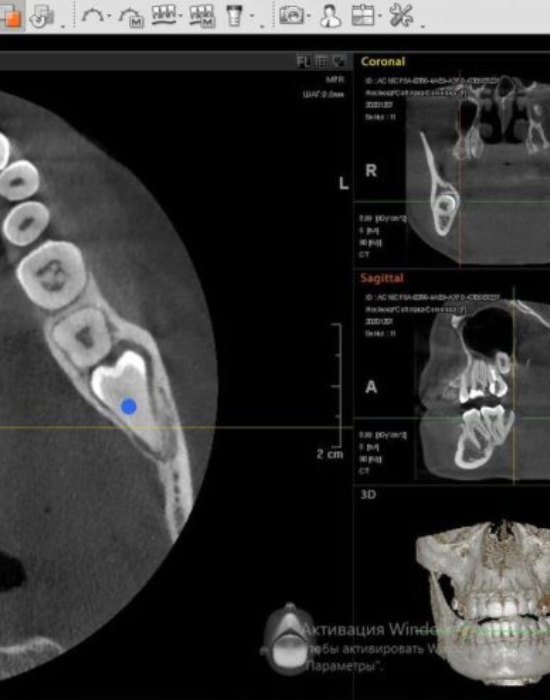

Особливості аналізу КТ зображень в клінічній практиці лікаря хірурга-стоматолога

✔️ Принцип роботи КПКТ, МСКТ, існуючі обмеження, вибір параметрів під кожен клінічний випадок

✔️ Хірургічно значущі анатомічні структури та їх варіабельність за даними КПКТ

✔️ Роль КПКТ у передопераційному плануванні хірургічних втручань

✔️Оцінка якості та морфології кісткової тканини за даними КПКТ

✔️ Варіанти артефактів зображень та як відрізнити від патології?